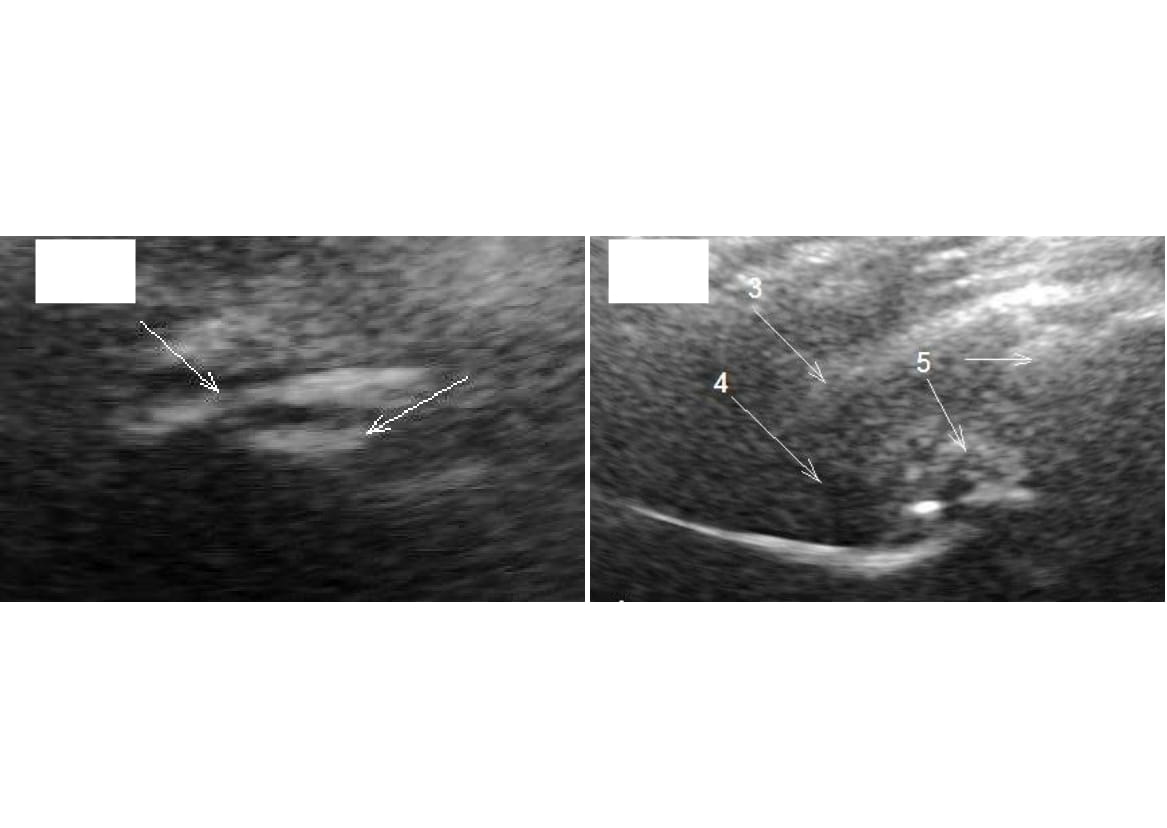

In US examination of hip joints of patients with III stage posttraumatic CA, the joint surfaces were visualized as fragments and lumps of different size, hypoechogenic cyst-like foci were differentiated. Acoustic density of some fragments was 180 (172;190) conv.un., cyst-like areas had low acoustic density – not more than 55 conv.un. (Fig. 2A). In the region of synovial medium of the joint, progressing pathological alterations were also seen: in result of degeneration, hyaline cartilage was practically not visualized or was determined as islets, there was tension with subsequent separation of fibrous membrane to fibers, synovial membrane of the capsule acquired heterogeneous structure and increased to 8.8 (7.7;10.0) mm (Fig. 2B). In result, echo-signs of pronounced synovitis were visualized ((thickness of the joint capsule 14 (11;18) mm).

Fig. 2. A sonogram of a patient S., 22 years old.

Diagnosis: III stage posttraumatic coxarthrosis:

А – standard scanning: femoral head is visualized as lumps and fragments 5 to 12 mm in size (shown by arrows), depth of US penetration was 13.7-20 mm, ossificate 6.9 mm in size, acetabulum contour not differentiated;

B – oblique-diagonal scanning: 3 – fibrous membrane of the joint capsule is 5-5.4 mm thick, 4 – joint capsule is 28.6 mm thick, 5 – lumps, fragments